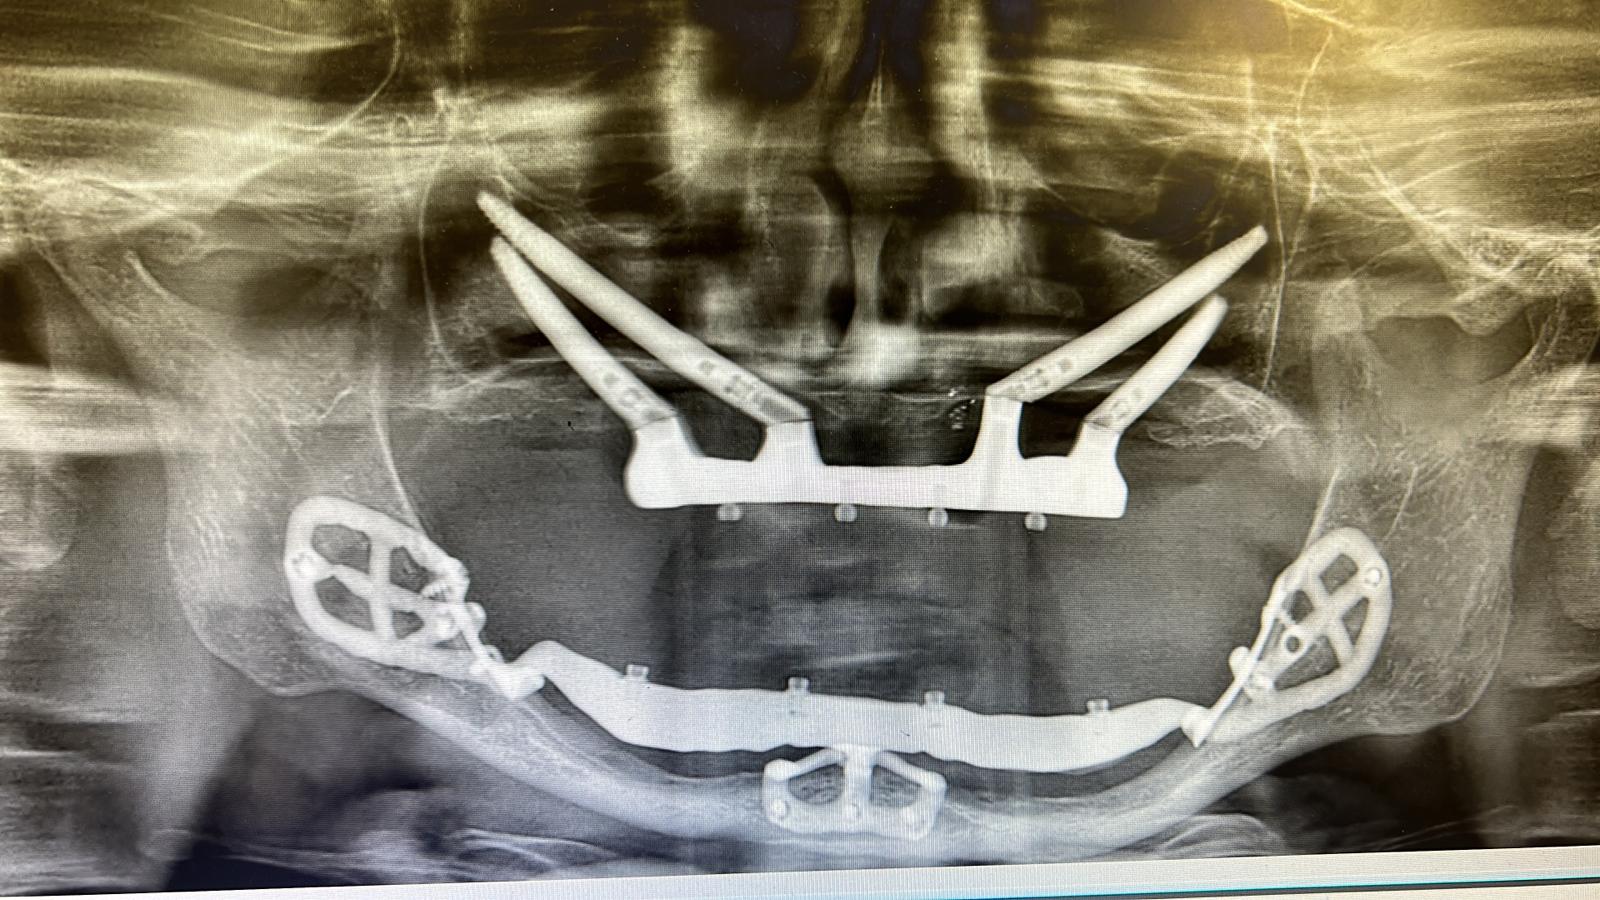

Dime radiologiche in posizione

Fig. 2. Dime radiologiche in posizione.